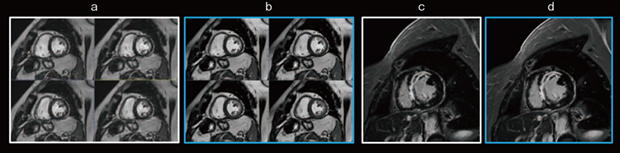

もう一つの技術である「AIR Recon DL」は,画質向上を目的としており,signal to noise ratio(SNR)を大幅に改善し,画像の尖鋭度を向上させる効果がある。心臓MRI検査のさまざまな撮像に適用可能であり,特に遅延造影やblack blood imagingなど,SNRの確保が難しい検査に効果を発揮する。AIR Recon DLにより,撮像時間を延長することなくノイズを低減し,空間分解能が低い撮像条件でもシャープな画質を得ることができ,心筋の微細な信号変化を明瞭に描出することができる(図1 c,d)。

図1 ディープラーニング画像再構成による画質改善効果

c:従来の遅延造影

d:AIR Recon DLを併用した遅延造影